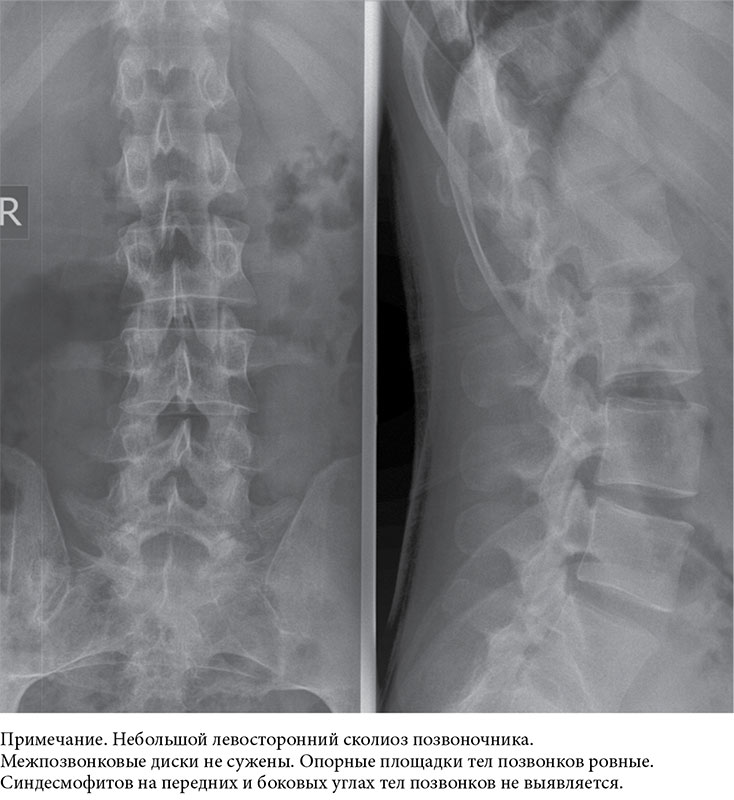

Медицинские снимки: рентген позвоночника сбоку